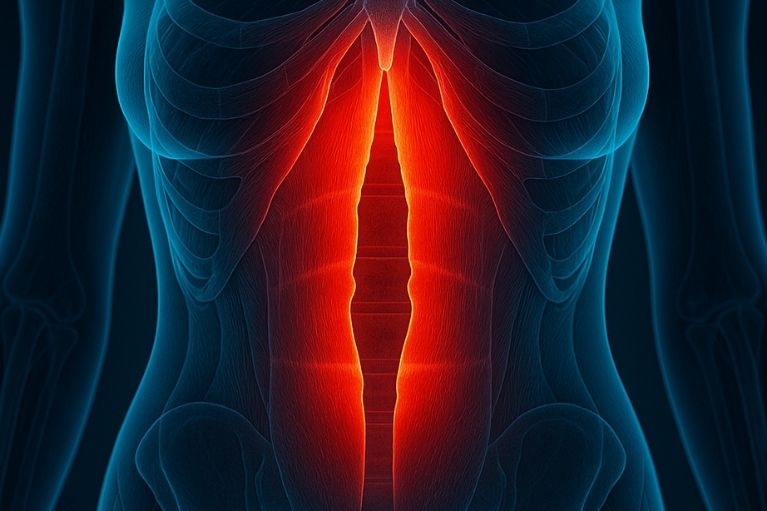

É a separação dos músculos retos do abdômen. Muito comum após a gravidez, mas ocorre também em outras situações. A correção por via robótica traz um resultado estético muito bom.